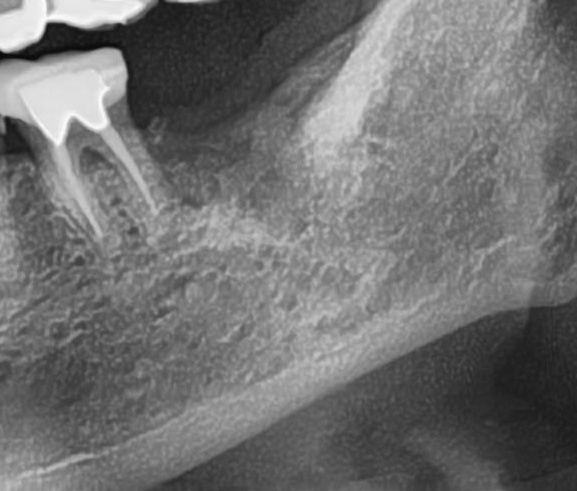

開けた穴に、専用道具を使ってネジを締めるように長さ2センチ程のインプラントを骨に埋め込んでいきます。

しっかりとインプラント埋め込まれた後は、動揺がないか、噛んだ時に当たらないかなどを確認して、最後にパノラマ写真を撮影して今回のオペは終了となりました。